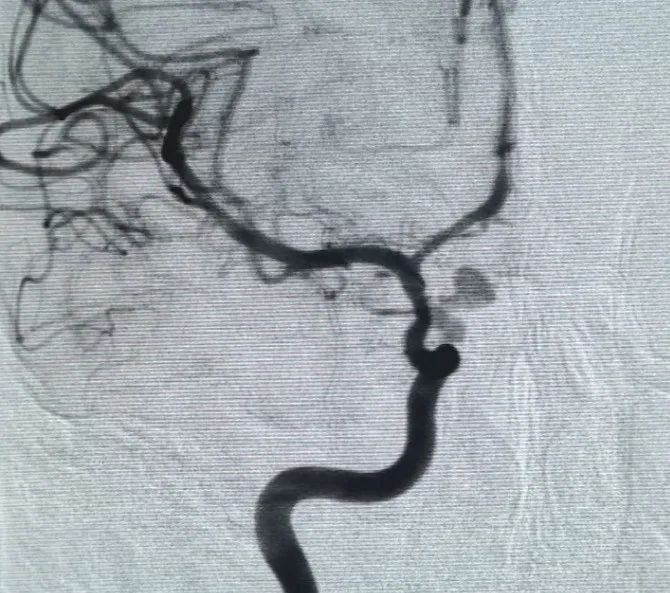

Un Perfiller®3mm × 6 cm bobina expansible y un Perfiller®A continuación se colocaron bobinas expansibles de 3mm x 2 cm para completar la oclusión del cuello. Posteriormente, un Nuva®Se administró un desván de flujo (TJED-D-5.0-16) y se desplegó a través del cuello del aneurisma. La angiografía de seguimiento en las vistas anteroposterior y lateral confirmó una excelente cobertura, buena aposición de la pared y clara radiopacidad, con marcado estancamiento del contraste.

El procedimiento se completó sin problemas, sin complicaciones, y el paciente se recuperó sin déficits neurológicos.

Este caso demuestra que Nuva®Junto con Perdenser®Y Perfiller®Coils, proporciona a los médicos una solución integrada y eficaz para el tratamiento de aneurismas desafiantes de la arteria carótida interna.